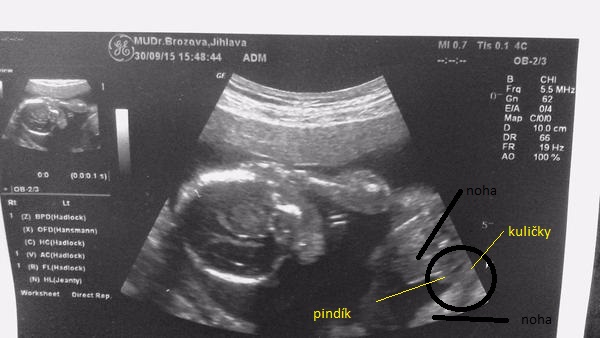

@zuziry : na tohle ti rekla holcicku ?? 🙊tak uvidíš třeba ji met budeš. ... já tam vidím výstavního pindika...i s kuličkami,ale jestli ti to řekla tak třeba holčičku mít budeš 😉ten 20 týden je docela přesný pokud jsou nožičky takhle zepředu. A kdyby to byl kluk,tak nevěš hlavu,ja tenkrát i plakala a dnes bych ho nevymenila za nic na světě, mám totiž také 3kluky...😉

@satynka Mně je pohlaví jedno 🙂. No ale jak jsem doma koukala na tu fotku, tak se mi taky zdá že to je kluk. Leda že by to byl kousek bříška, ale to se mi nezdá tak symetrické ( vyznačím to )...

Já tam taky vidím pindíka 😉 .

Tak ještě jak to vidím já 🙂, třeba to i pomůže někomu se lépe orientovat ve vlastních fotkách 😉

tady je hezky znázornění,ze může byt pindik i kavove zrno,😃myslím tím ty kuličky. ..ale říkáte ze je to kluk,tak to kluk je,myslím ze je to moc hezká fotecka 👍😉